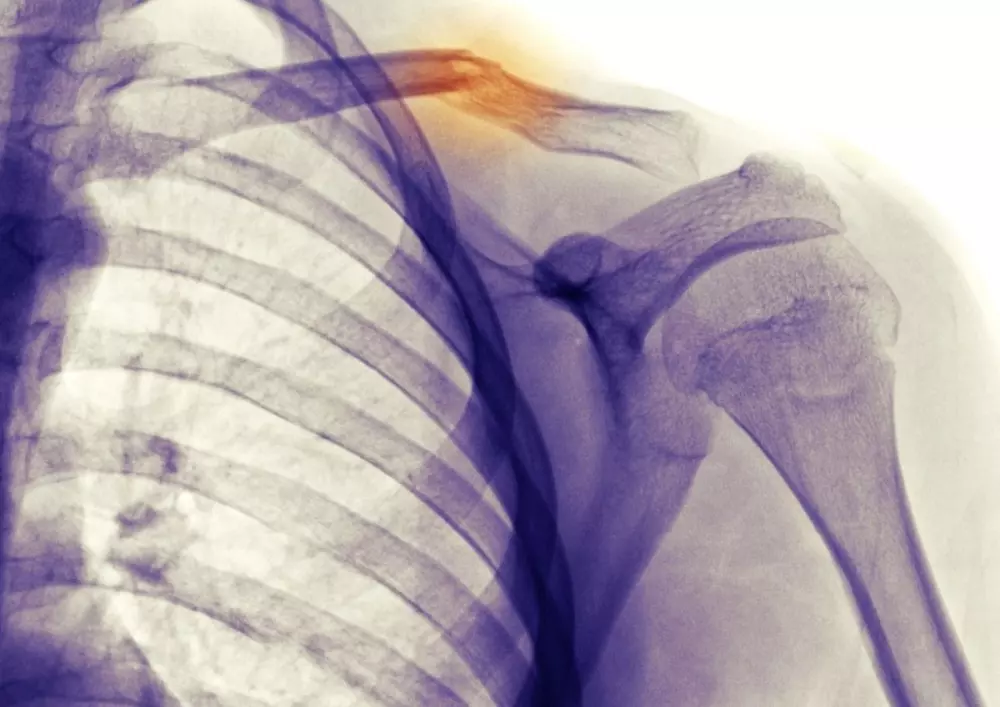

Rehabilitacja po złamaniu obojczyka

W dziele „Z praktyki gabinetu” znajdą Państwo artykuł pt. „Postępowanie fizjoterapeutyczne po złamaniu obojczyka”. Najczęściej do urazu dochodzi w okresie noworodkowym, podczas porodu. W artykule omówiona została anatomia obojczyka, dzięki której łatwiejsze będzie przybliżenie tego problemu. Gdy uraz wymaga postępowania operacyjnego, usprawnianie prowadzone jest wieloetapowo. Rehabilitacja po złamaniu obojczyka wymaga współpracy z lekarzem prowadzącym czy lekarzem, który prowadził operację. Ponadto, dla jej powodzenia ważne jest zaangażowanie pacjenta i terapia domowa, która jest pomocna w utrzymaniu efektu usprawniania.